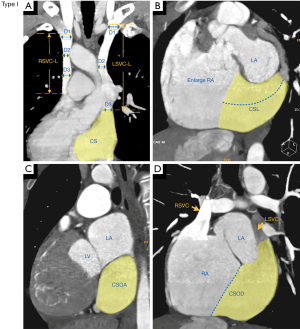

The cases were classified into the following 4 types based on the presence or absence of left brachiocephalic vein (LBCV), the presence or absence of an anastomotic vein bridging the bilateral SVC, and the drainage pattern of the LSVC: (I) type I, DSVC without LBCV, LSVC drainage into the right atrium via the coronary sinus (see Figure 1); (II) type II, DSVC with LBCV, LSVC drainage into the right atrium via the coronary sinus (see Figure 2A,2B); (III) type III, DSVC without LBCV, LSVC drainage into the right atrium via an anastomotic vein bridging the LSVC and RSVC (see Figure 2C,2D); and (IV) type IV, DSVC with LBCV, LSVC drainage into the right atrium via an anastomotic vein (see Figure 2E,2F).

The following quantitative measurements taken from the CT images (see Figure 1): the length of the RSVC (RSVC-L) was measured from the confluence of the left and right brachiocephalic veins (or from the level of the first sternocostal joint on the right if there was no LBCV) to the entrance of the right atrium; the length of the LSVC (LSVC-L) was measured from the level of the LBCV opening (or the level of the first sternocostal joint on the left if there was no LBCV), to either the coronary sinus entrance to the LSVC or the opening of the bilateral SVC anastomosis; the diameter of the bilateral SVC was obtained by calculating the average of the diameter of the proximal, middle and distal segments of the bilateral SVC at the best display slice; the area of the bilateral SVC was measured at the third segment, from the RSVC to the right atrial entrance; the length of the coronary sinus (CSL) was measured on the oblique coronal plane of the coronary sinus; the diameter of the coronary sinus ostium (CSOD) was measured at the coronary sinus entrance on the oblique sagittal view; and the area of coronary sinus ostium (CSOA) was measured on the transverse orientation of the coronary sinus ostium.

According to our newly proposed classification system, the distribution of the 128 DSVC patients was as follows: type I, 66 of 128 (51.6%) (see Figure 1); type II, 43 of 128 (33.6%) (see Figure 2A,2B); type III, 15 of 128 (11.7%) (see Figure 2C,2D); and type IV, 4 of 128 (3.1%) (see Figure 2E,2F). In the majority of patients (type I and type II; 85.2%), the LSVC drained into the right atrium via the coronary sinus.